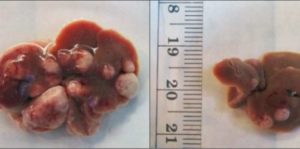

Immagine: a sinistra cellule del cancro al fegato non trattate, a destra cellule del cancro al fegato trattate con (dsRNA). Credit:…